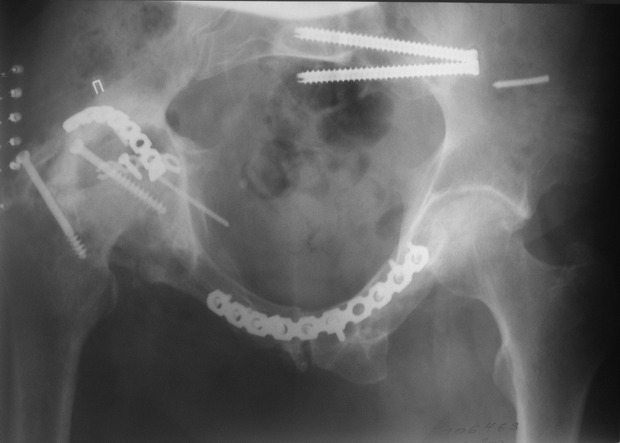

Пациент 49 лет, паровозная травма 23.2.2006, получил вертикальная нестабильное повреждение таза, разрыв левого крестцово-подвздошного сочленения, перелом лонной, седалищной костей слева, T-образный оскольчатый перелом правой вертлужной впадины с переломом заднего края, вывих правого бедра, посттравматическая пояснично-крестцовая плексопатия с обеих сторон, паралич мышц правой голени.

В день травмы - вправление вывиха, скелетное вытяжение, 14.3.2006 чрескостный остеосинтез таза. 20.4.2006 остеосинтез правой вертлужной впадины пластинами, осложнившийся нагноением межмышечной гематомы правой ягодичной области. Получал консервативное лечение, было достигнуто полное заживление раны. 24.7.2006 введены илиосакральные винты слева. С декабря 2006 года и по настоящее время ходит на костылях без опоры на правую ногу. Планируется THA. Помогите определиться с вариантом костной пластики? И какую укрепляющую конструкцию использовать?